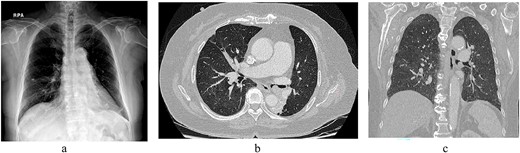

A 76-year-old female patient presented to the hospital with dyspnea and coughing. A chest X-ray (Fig. 1a) revealed a possible tumor in the left main bronchus and atelectasis of the left lower lobe. A chest computed tomography scan confirmed an endobronchial tumor obstructing the left lower lobe bronchus that had grown toward the main bronchus to the point of near complete obstruction. A malignant tumor in the endobronchial region was suspected (Fig. 1b and c). Bronchoscopy was performed and revealed an endobronchial tumor with a smooth surface that obstructed most of the left main bronchus (Fig. 2). Blood vessels were visible on the tumor surface. The tumor did not appear amenable to endobronchial treatment or resection. The results of bronchoscopy suggested a benign tumor, although malignant disease could not be ruled out. Surgery was chosen for treatment.

(a) Chest radiogram shows a possible tumor in the left main bronchus and atelectasis of the left lower lobe. (b) A chest computed tomography scan confirmed an endobronchial tumor obstructing the left lower lobe bronchus that was growing toward and nearly completely blocked the main bronchus. (c) Coronal view.